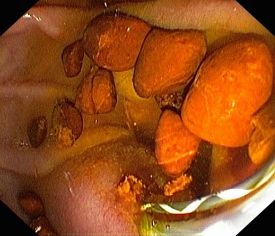

- Entfernung von Gallensteinen, mechanische Steinzertrümmerung (Lithotrypsie)

Die Untersuchung wird in Bauchlage durchgeführt. Aus Sicht des Patienten ähnelt sie der Magenspiegelung, allerdings wird das Endoskop tiefer in den Zwölffingerdarm platziert, so dass die Gallengangsmündung (Papille) zu sehen ist. In diese wird Kontrastmittel eingespritzt, und so die Gallengänge unter Röntgendurchleuchtung sichtbar gemacht.

Ist beispielsweise ein Abflusshindernis in den Gängen durch Gallensteine vorhanden, kann dies nun endoskopisch mit verschiedenen Methoden beseitigt werden.